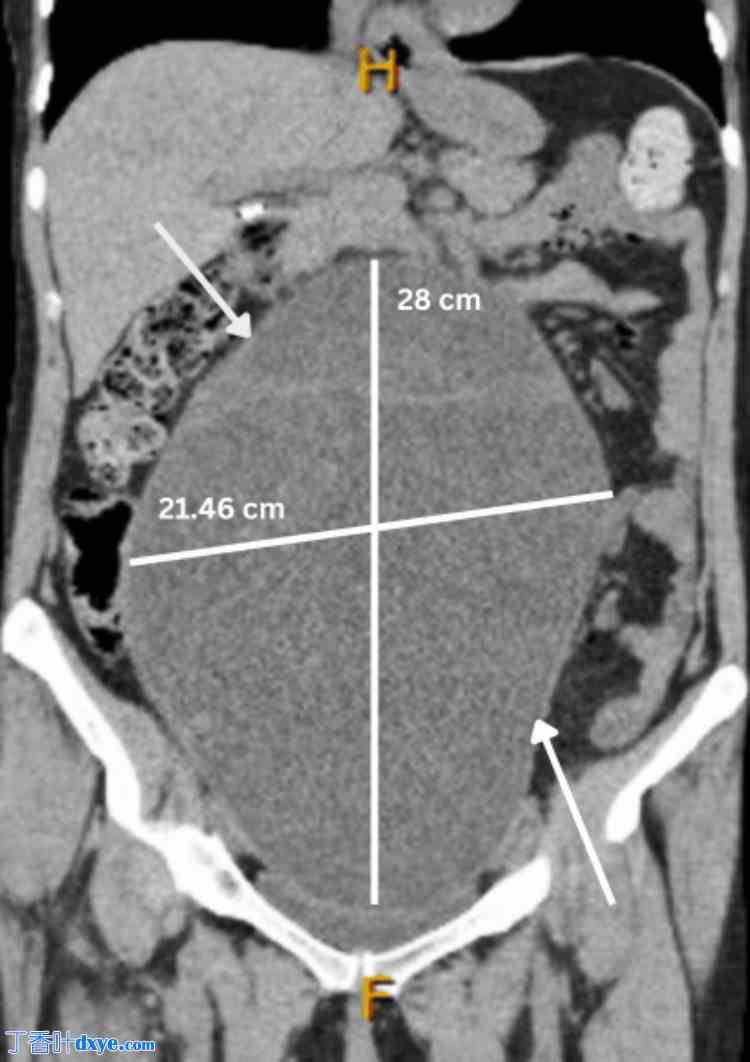

图 1. 右侧边缘性卵巢肿瘤的冠状面 MRI 图像,大小为 21.46 cm x 28 cm。

1.jpg